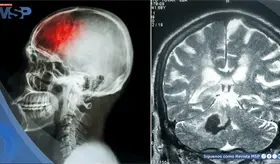

El intenso dolor torácico no fue una recaída ni metástasis, sino un daño óseo provocado por la reirradiación. Los huesos, debilitados por la radioterapia previa y la reirradiación, estaban perdiendo su capacidad de curarse adecuadamente.